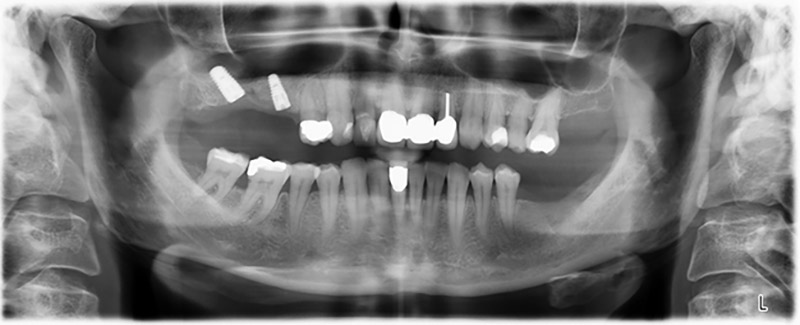

La paciente de 59 años presentaba una periodontitis avanzada, describía una desagradable sensación y un mal gusto proveniente del primer cuadrante. La evaluación clínica mostró en general marcadas profundidades de bolsa y una degeneración ósea muy avanzada en las regiones 16 y 14. El estudio radiológico corroboró estos resultados (figura 1). Las piezas dentales 16 y 14 no podían conservarse.